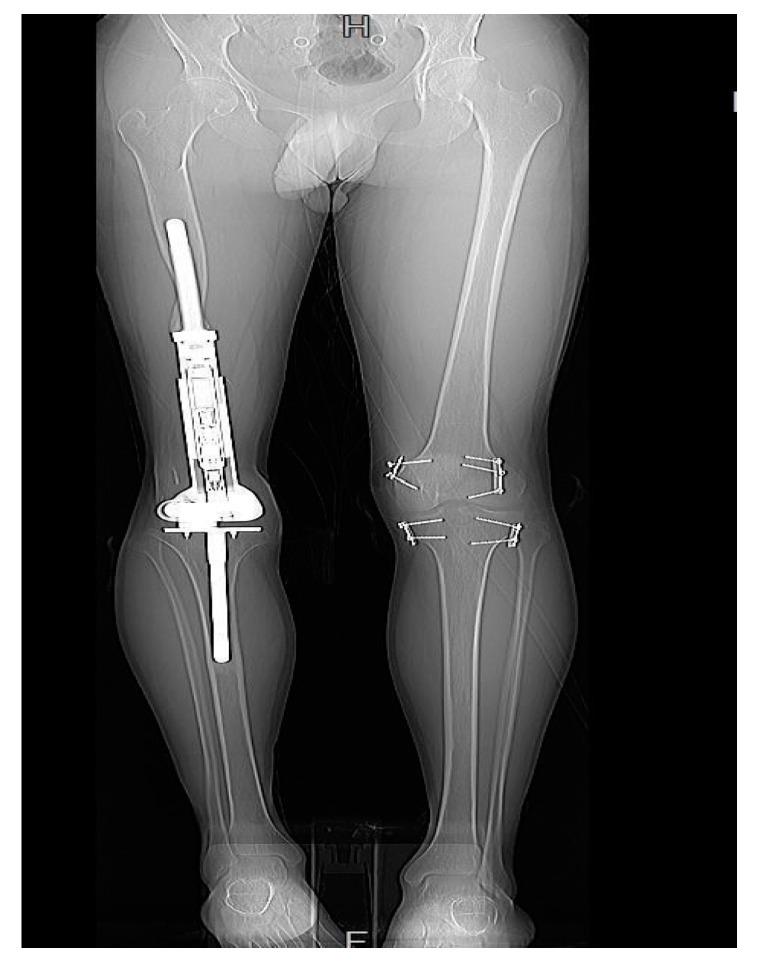

Tibia Multiplanar Deformities and Growth Disturbance Following Expandable Endoprosthetic Distal Femur Replacement.

Background: Expandable distal femur endoprosthesis (EDFE) is commonly used to compensate for the loss of the distal femoral epiphyseal plate in skeletally immature children who have undergone surgical resection of bone malignancies. However, the effect of the passive tibial component of the EDFE on tibial growth has not been extensively studied in the literature. This study aims to delineate the type, frequency, and associated risk factors of multiplanar proximal tibial deformities in skeletally immature children following the use of the expandable distal femur endoprosthesis (EDFE). Moreover, we plan to detect how these deformities influence the long-term functionality of the endoprosthesis in defining the need for subsequent implant revision or further surgical management. Patients and Methods: A total of 20 patients aged (7−12) years underwent expandable distal femur replacement. Two types of implants were used: Juvenile Tumor System (JTS) non-invasive prosthesis in 14 patients, and Modular Universal Tumor and Revision System (MUTARS)® Xpand Growing Prostheses in six patients. A scanogram and CT scan documented the measurements of longitudinal and multiplanar growth as leg length discrepancy (LLD), femur length discrepancy (FLD), tibia length discrepancy (TLD), and the yield values of rotational, sagittal, and coronal deformities of the tibia. The patients were followed up to assess the need for further management. Sex, age, size of tibial plate perforation, and type of implant used were studied for possible correlation with deformities or growth disturbance. Results: The patients were followed up for a mean of 3 (2−7) years. A total of 14 patients, (10 JTS, 4 implant cast) had a tibial deformity and/or growth disturbance. A single patient was found to have all deformities (growth, rotational, coronal, and sagittal). Fourteen patients were found to have an LLD ranging from 5.3 to 59 mm (median 21 mm), 12 had a TLD from 3 to 30 mm, (median 10 mm), and 11 patients showed evidence of malrotation from 6 to 32 degrees (median 11 degrees). TLD was found to contribute entirely to LLD in three patients, and >50% of LLDs in seven patients. All LLDs were treated conservatively, except in three patients; two received contralateral tibia epiphysiodesis and one received revision with a new implant. A single patient had a posterior tibia slope angle (PTSA) of −2.8 degrees, and three patients had a coronal deformity with a mean medial proximal tibia angle (MPTA) of 80.3 (77−83 degrees). Conclusions: Tibial growth disturbance and multiplanar deformities occur in the majority of patients following EDFE replacement, exacerbating LLD. Yet, these disturbances may be well tolerated, managed conservatively, and rarely mandate endoprosthetic revision or subsequent corrective surgery. Age at the time of surgery was found to be the only significant contributor to the development of tibia growth disturbance.

共有20例年龄在7至12岁的患者接受了可扩张型股骨远端置换术。使用了两种类型的植入物:14例患者使用了青少年肿瘤系统(JTS)非侵入性假体,6例患者使用了模块化通用肿瘤与翻修系统(MUTARS)® Xpand生长型假体。通过扫描图和CT扫描记录纵向和多平面生长的测量数据,包括腿长差异(LLD)、股骨长度差异(FLD)、胫骨长度差异(TLD)以及胫骨旋转、矢状面和冠状面畸形的屈服值。对患者进行随访以评估是否需要进一步治疗。研究了性别、年龄、胫骨板穿孔大小和使用的植入物类型与畸形或生长障碍的可能相关性。

结果

患者平均随访3(2至7)年。共有14例患者(10例JTS,4例植入石膏)出现胫骨畸形和/或生长障碍。发现1例患者存在所有畸形(生长、旋转、冠状面和矢状面)。发现14例患者的LLD范围为5.3至59毫米(中位数21毫米),12例患者的TLD为3至30毫米(中位数10毫米),11例患者显示有6至32度的旋转不良(中位数11度)。发现3例患者的LLD完全由TLD导致,7例患者的LLD超过50%由TLD导致。除3例患者外,所有LLD均采用保守治疗;2例接受对侧胫骨骨骺阻滞术,1例接受新植入物翻修术。1例患者的胫骨后倾角(PTSA)为 -2.8度,3例患者存在冠状面畸形,胫骨近端内侧平均角(MPTA)为80.3(77至83度)。